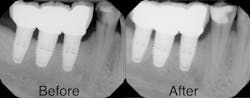

Upon clinical and radiographic examination, it was determined that the patient had a combination of caries, inflamed gingiva from desiccation, and loss of vertical dimension (figure 4). Xerostomia and insufficient home care were implicated in the patient’s elevated caries rate, as well as the presence of implants leading to implant-induced caries.